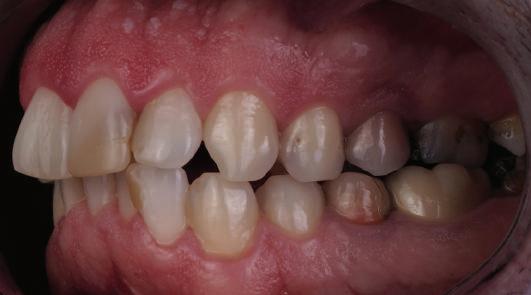

Dental Tribune Bulgarian Edition / октомври 2022 г.16 клиничен случай с алайнери Г орният латерален ре зец е вторият найчесто вродено липсващ зъб.1,2 Поради разполо жението му във видимата зона на усмивката лечение то на подобни случаи нала га мултидисциплинарен под ход, целящ отличен функцио нален и естетичен резултат. Налице са няколко лечебни мо далности, свързани с различ но разпределение на място то: първият вариант е орто донтско отваряне на място и възстановяване на липсва щия зъб с конструкция, под държана от съседните зъби3 или от имплант4, докато при втория подход разстоянията се затварят и премоларът заема мястото на канина.5 Изборът на лечебен подход трябва да бъде направен съв местно от зъболекар и паци ент въз основа на очакванията на последния и предвиди мостта на лечението. Множе ство фактори влияят върху това решение, като напри мер типа малоклузия, размера, формата и цвета на кучеш ките зъби6, оклузалните вза имоотношения (овърджет и овърбайт), лицевия профил, дължината на зъбната дъга и несъответствията в разме ра на зъбите.7 В настоящата публикация се разглежда случаят на жена в зряла възраст с вродена лип са на горен ляв латерален резец. Бяха приложени про зрачни алайнери за отваряне на място за единичен им плант и бяха постигна ти функционална оклузия и отлична естетика. ПРЕДСТАВЯНЕ НА СЛУЧАЯ Диагноза Пациентката бе на 32 годи ни, когато лечението започна, и първоначалното ѝ състоя ние бе следното (фиг. 1–3): липсващ горен ляв латерален резец; клас II, подклас I малоклузия; отклонение на горната сре динна линия вляво; Доклад на клиничен случай ЛЕЧЕНИЕ С АЛАЙНЕРИ НА ПАЦИЕНТ С АГЕНЕЗИЯ НА ЛАТЕРАЛЕН РЕЗЕЦ Д-р Iro Eleftheriadi и д-р Christodoulos Laspos, Гърция и Кипър Фиг. 1a–h Предоперативни лицеви и интраорални снимки. Фиг. 2a–e Дигитални модели преди началото на лечението. Фиг. 3 Панорамна снимка преди лечението. Фиг. 1a Фиг. 1d Фиг. 1f Фиг. 2a Фиг. 2d Фиг. 2b Фиг. 2e Фиг. 3 Фиг. 2c Фиг. 1b Фиг. 1e Фиг. 1g Фиг. 1h Фиг. 1c

Dental Tribune Bulgarian Edition / октомври 2022 г. 17клиничен случай с алайнери леко струпване в долната че люст; несъответствие по Болтън (мандибуларен излишък от 3.06 мм във фронталната зона и общо 1.47 мм); издължено лице с лицева аси метрия; конвексен профил с ретруди рана долна челюст и проми нентен нос. На мястото на зъб #46 бе на лице имплант, а зъби #16 и 26 са ендодонтски лекувани. Тези зъби бяха асимптоматич ни, затова бе взето решение да се прави релечение само при нужда. Мъдреците липсваха. Анализът на телерентгеногра фията (фиг. 4) показа ретрог натна мандибула (SNB: 74.2°) и нормална инклинация на резците както в

Цели на лечението и лечебен план Целите на лечението бяха следните: нивелиране и подреждане на зъбите и в двете зъбни дъги; отваряне на пространство за липсващия латерален резец; коригиране на отношенията при канините и моларите до клас I; и корекция на отклонението на срединната линия. Лечебният план включваше: корекция на отношенията при кучешките зъби и мола рите до клас I с дистализира не на максилата; отваряне на пространство в областта на #22 за поставя не на единичен имплант; корекция на срединната ли ния; и създаване на място за раз ширяване на зъб #12 и апрок симална редукция в долната челюст с цел подобряване на несъответствието по Болтън и осигуряване на подобра оклузия. Изпълнение на лечебния план Този случай бе изпълнен със системата за алайнери Invisalign (Align Technology). Одобреният първоначален лечебен план предвиждаше 49 алайне ра с дистализиране на задни те горни зъби до клас I (прибли зително с около 3.5 мм; фиг. 5). За бъдещия имплант в областта на липсващия латерал бе планирано пространство от 6.5 мм, докато във фронталния сегмент на долната челюст бе предвидена апроксимална редук ция. В дясната страна бутон за ластици клас II бе поставен на зъб #47 вместо на зъб #46, за да не се увреди короната на импланта. Понеже пациентката жи вееше в чужбина,

следните казуси: недобра оклу зия в дисталните зони по вре ме на дистализирането на гор ната челюст и накланяне на зъб #21 (фиг. 7). Последното се дължи на липсата на компози тен атачмънт на този зъб, каквото не бе зададено в пър Фиг. 4 Телерентгенография и цефалометричен анализ преди началото на лечението. Фиг. 5a–e Одобреният първоначален лечебен план. Фиг. 6a–h Снимки по време на лечението, показващи нуждата от внасяне на някои корекции. Фиг. 4 Фиг. 5a Фиг. 5d Фиг. 6a Фиг. 6d Фиг. 6f Фиг. 6b Фиг. 6e Фиг. 6g Фиг. 6h Фиг. 6c Фиг. 5e Фиг. 5b Фиг. 5c

Dental Tribune Bulgarian Edition / октомври 2022 г.18 воначалния план. Тези пробле ми бяха адресирани чрез допъл нителна поръчка на алайнери с торк контрол и зададено екст рудиране на задните зъби с цел установяване на добри оклузал ни контакти в дисталните об ласти, като бяха предвидени и оптимизирани атачмънти с контрол над корените за корекция на ангулацията на макси ларните резци (фиг. 8). Резултати от лечението Панорамната рентгено графия след ортодонтското лечение показа благоприятна паралелна позиция на съседни те зъби, подходяща за поставя не на имплант в областта на #22, както и конвергенция на ко рените на зъби #44 и 45 (фиг. 9), но преценихме, че няма да от деляме допълнително лечебно време за коригирането ѝ поради факта, че пациентката бе мно го доволна от постигнатия до момента резултат. След при ключване на лечението бяха постигнати отлични взаимо отношения клас I при мола рите и канините, а срединни